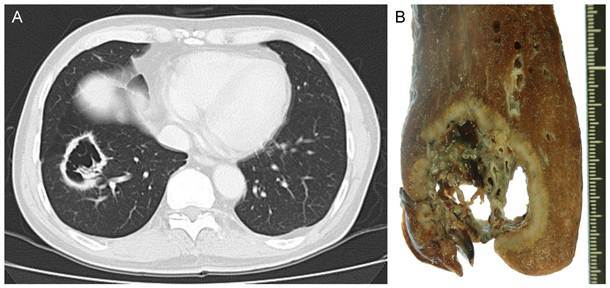

CA Broncogênicos que CAVITAM?

EPIDERMOIDE

GRANDES CÉLULAS